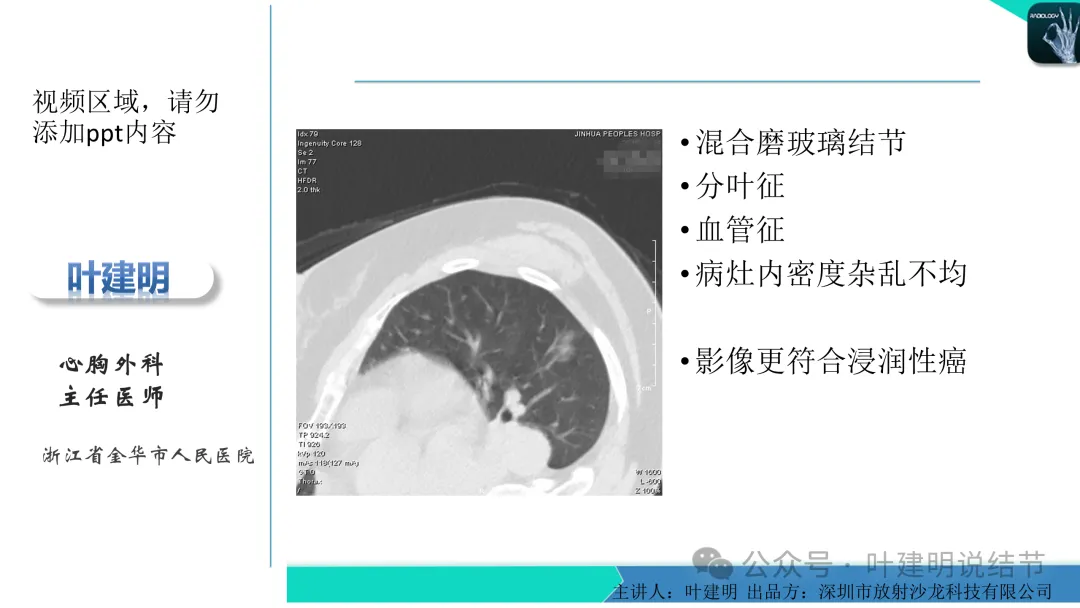

早在2020年时,我受邀在《放射沙龙》做过一个系列的精品课,当时专门总结分析过各类良恶性肺结节与肿块的影像特征,这是当时关于微浸润性腺癌影像特征的分析,今天看来仍基本不太需要改变,大家有兴趣的可以参考: